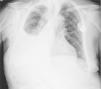

Se trata de un varón de 85 años, exfumador, con enfermedad pulmonar obstructiva crónica leve, fibrilación auricular y portador de marcapasos por enfermedad del seno diagnosticado de un urotelioma multifocal de vejiga tratado mediante resección transuretral y 6 instilaciones de BCG. Un año más tarde, acude a urgencias por dolor torácico de características pleuríticas y aumento de disnea, evidenciando en la radiografía de tórax (fig. 1) derrame pleural derecho. Se instaura antibioterapia empírica con amoxicilina/clavulánico e ingresa en neumología para ampliar el estudio con una tomografía computarizada (TC) torácica y una toracocentesis diagnóstica. En la primera describen un extenso derrame pleural derecho con atelectasia pasiva del lóbulo inferior ipsilateral, un granuloma calcificado subpleural en el lóbulo inferior izquierdo y adenopatías prevasculares e hiliares, sugestivas de un proceso granulomatoso previo. En la toracocentesis obtuvimos un líquido pleural turbio, tipo exudado con adenosin deaminasa (ADA) elevada (63,9 U/l) y predominio de células mononucleares (85%). No realizamos biopsia pleural dada la alta probabilidad de que se tratase de una infección por Mycobacterium, en virtud de las características del líquido obtenido. El cultivo del mismo fue positivo para M. bovis, estableciéndose el diagnóstico de derrame pleural por M. bovis secundario a la instilación endovesical de BCG. El paciente recibió tratamiento durante 6 meses con isoniacida, rifampicina y etambutol con buena respuesta clínica y resolución del derrame pleural, sin presentar efectos adversos a la medicación.